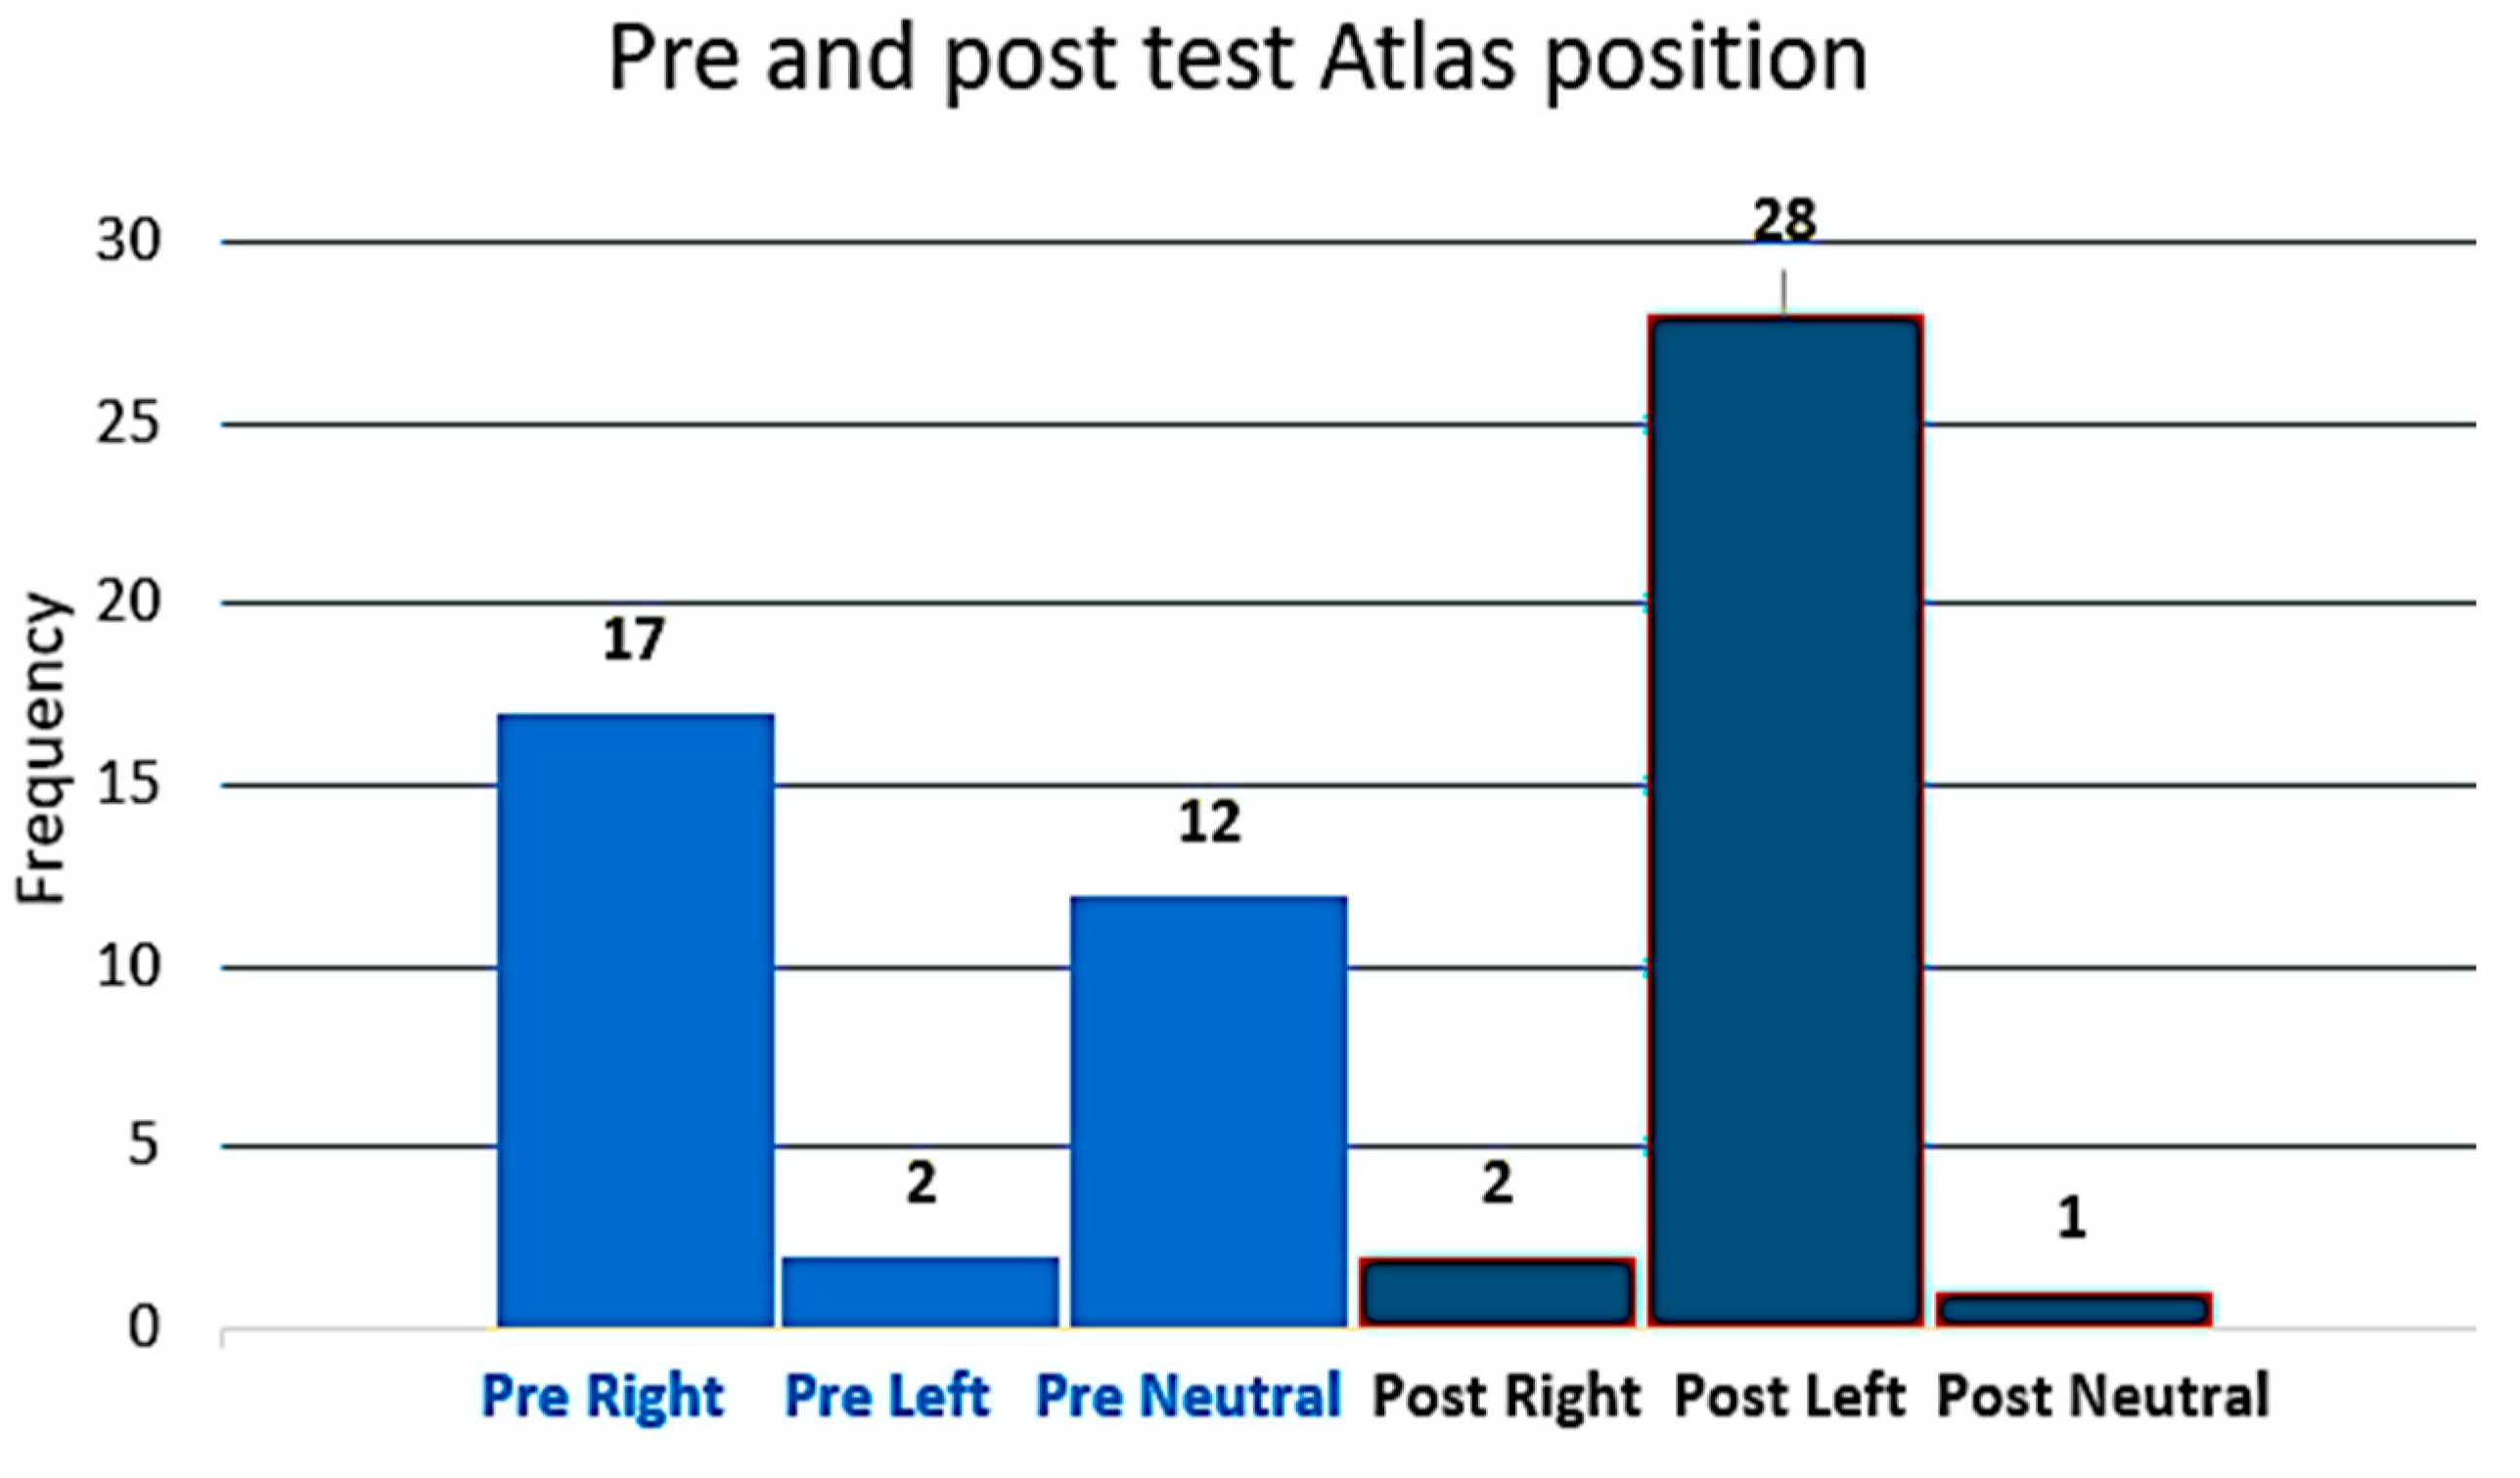

3.1. The Position of the Atlas Is Measured with Atlas Transverse Process Palpation

3. Results